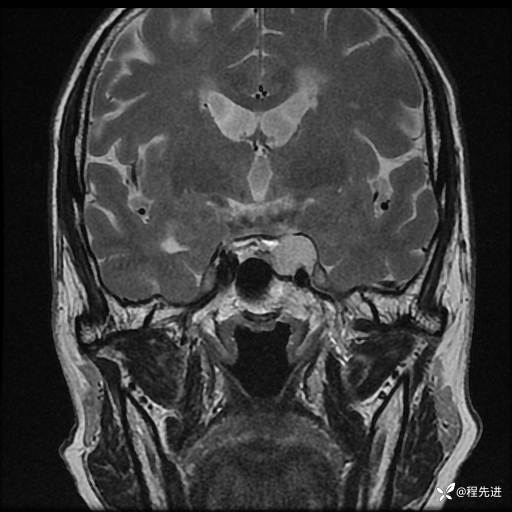

MRI平扫+增强:

T1增强: